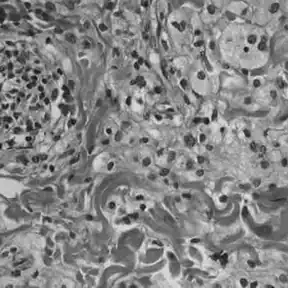

La maladie de Chester-Erdheim se distingue de l'histiocytose langerhansienne sur plusieurs points :

- elle n'est pas mise en évidence, contrairement à l'histiocytose langerhansienne, par un marquage à la protéine S-100 ou au CD 1a[13]

- une analyse du cytoplasme en microscopie électronique ne révèle pas de granules de Birbeck[13]

- les échantillons tissulaires montrent des infiltrations xanthomateuses ou xanthogranulomateuses par des histiocytes spumeux (gorgés en graisses), dans un environnement habituellement fibrosé.